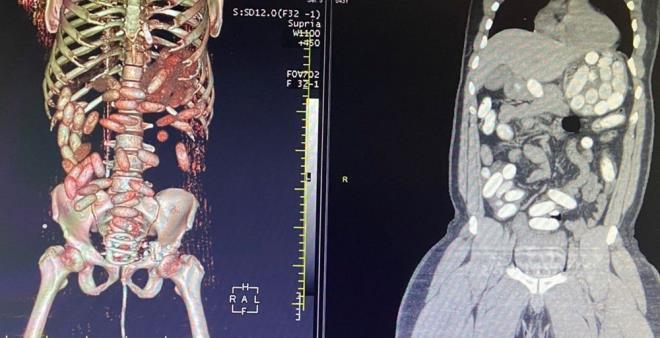

6. Yolcuda, 'yutucu' tespit cihazı ve ardından sağlık kuruluşunda yapılan muayene sonucu 48 adet kapsül ve toplam ağırlığı 760 gram kokain ele geçirildi.

Yolcuda, 'yutucu' tespit cihazı ve ardından sağlık kuruluşunda yapılan muayene sonucu 48 adet kapsül ve toplam ağırlığı 760 gram kokain ele geçirildi.